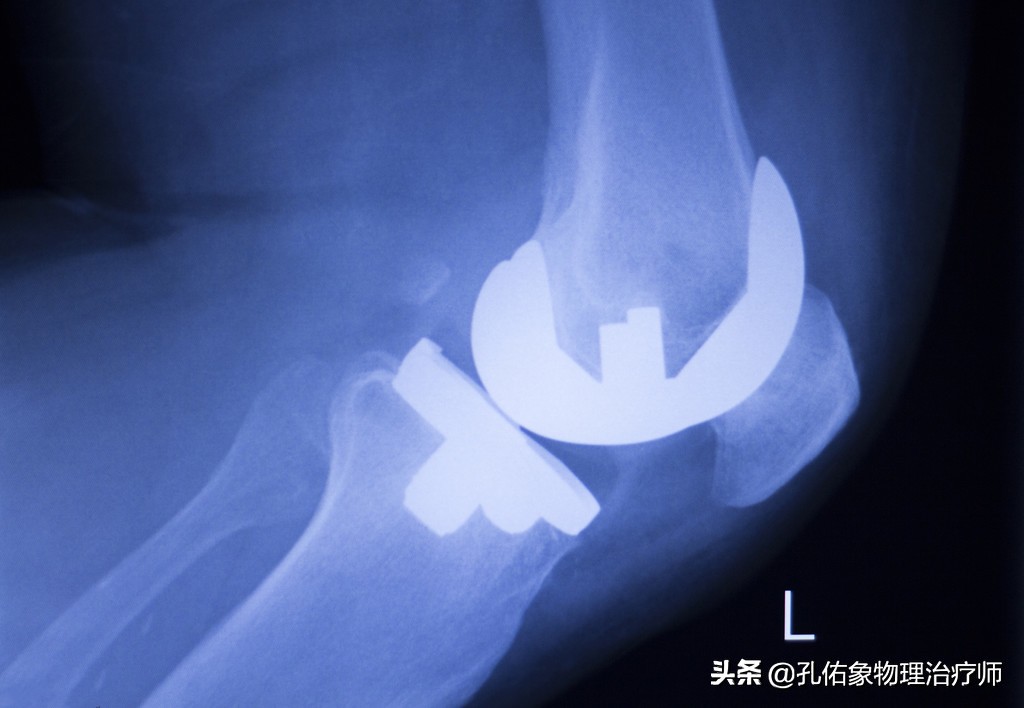

这种退行性的骨性关节病,必须要经过手术,经过术后康复才会好转;每天都会遇到这样的人群,说明发病的人越来越多,若是现在的你就有膝痛,千万别忽视治疗,否则将来的不久,你必定会不知不觉的就挤进这个行列。

膝关节痛骨性关节炎的治疗方法,膝骨性关节炎的手法治疗视频

膝痛在早期时,往往只体现出局部的疼痛,局部的炎症肿胀;但是随着自身的不注意,慢慢的力学改变,膝盖骨与大腿骨撞击就会引起膝盖骨下面的软骨损伤,逐年累月的血液循环障碍、骨质增生、骨赘形成;到这个时候要解决问题,只有通过手术,关节镜下处理或是直接用一个假的膝关节换进去。

我目前接诊着一个病人,还是医务工作者,才年仅42岁呀,就把膝关节给换了;因为我上面所写的的,在她身上都可以淋淋尽致的体现出来。

要是你在刚发现膝痛时,就早早选择正确恰当的方法治疗,绝对可以避免将来的手术。